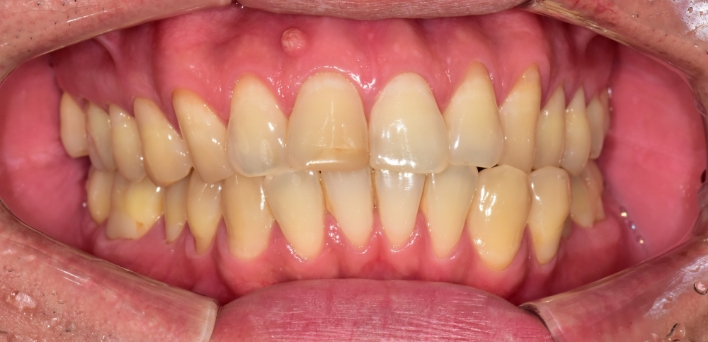

우리 얼굴에서 미소는 첫인상을 좌우합니다. 이런 좋은 인상을 위해 라미네이트를 고려 중이시라면,

많은 것들을 고려해야 합니다. 라미네이트 시 무조건 하얗고, 얇기만 한 치아가 좋은 것은 아닙니다.

개개인의 얼굴마다 비율에 맞게 이상적인 치아의 형태가 있습니다.

더서울치과의원은 정확한 안모 분석을 통한 프로파일 예측 치료로 심미성은 물론 치아 본연의 기능 회복까지 가능하도록

안면 근육과 기능, 치아 형태, 비율, 크기, 교합, 색감 등 전반적인 비율을 맞추어 본인에게 잘 맞는 치아의 형태로 복원합니다.